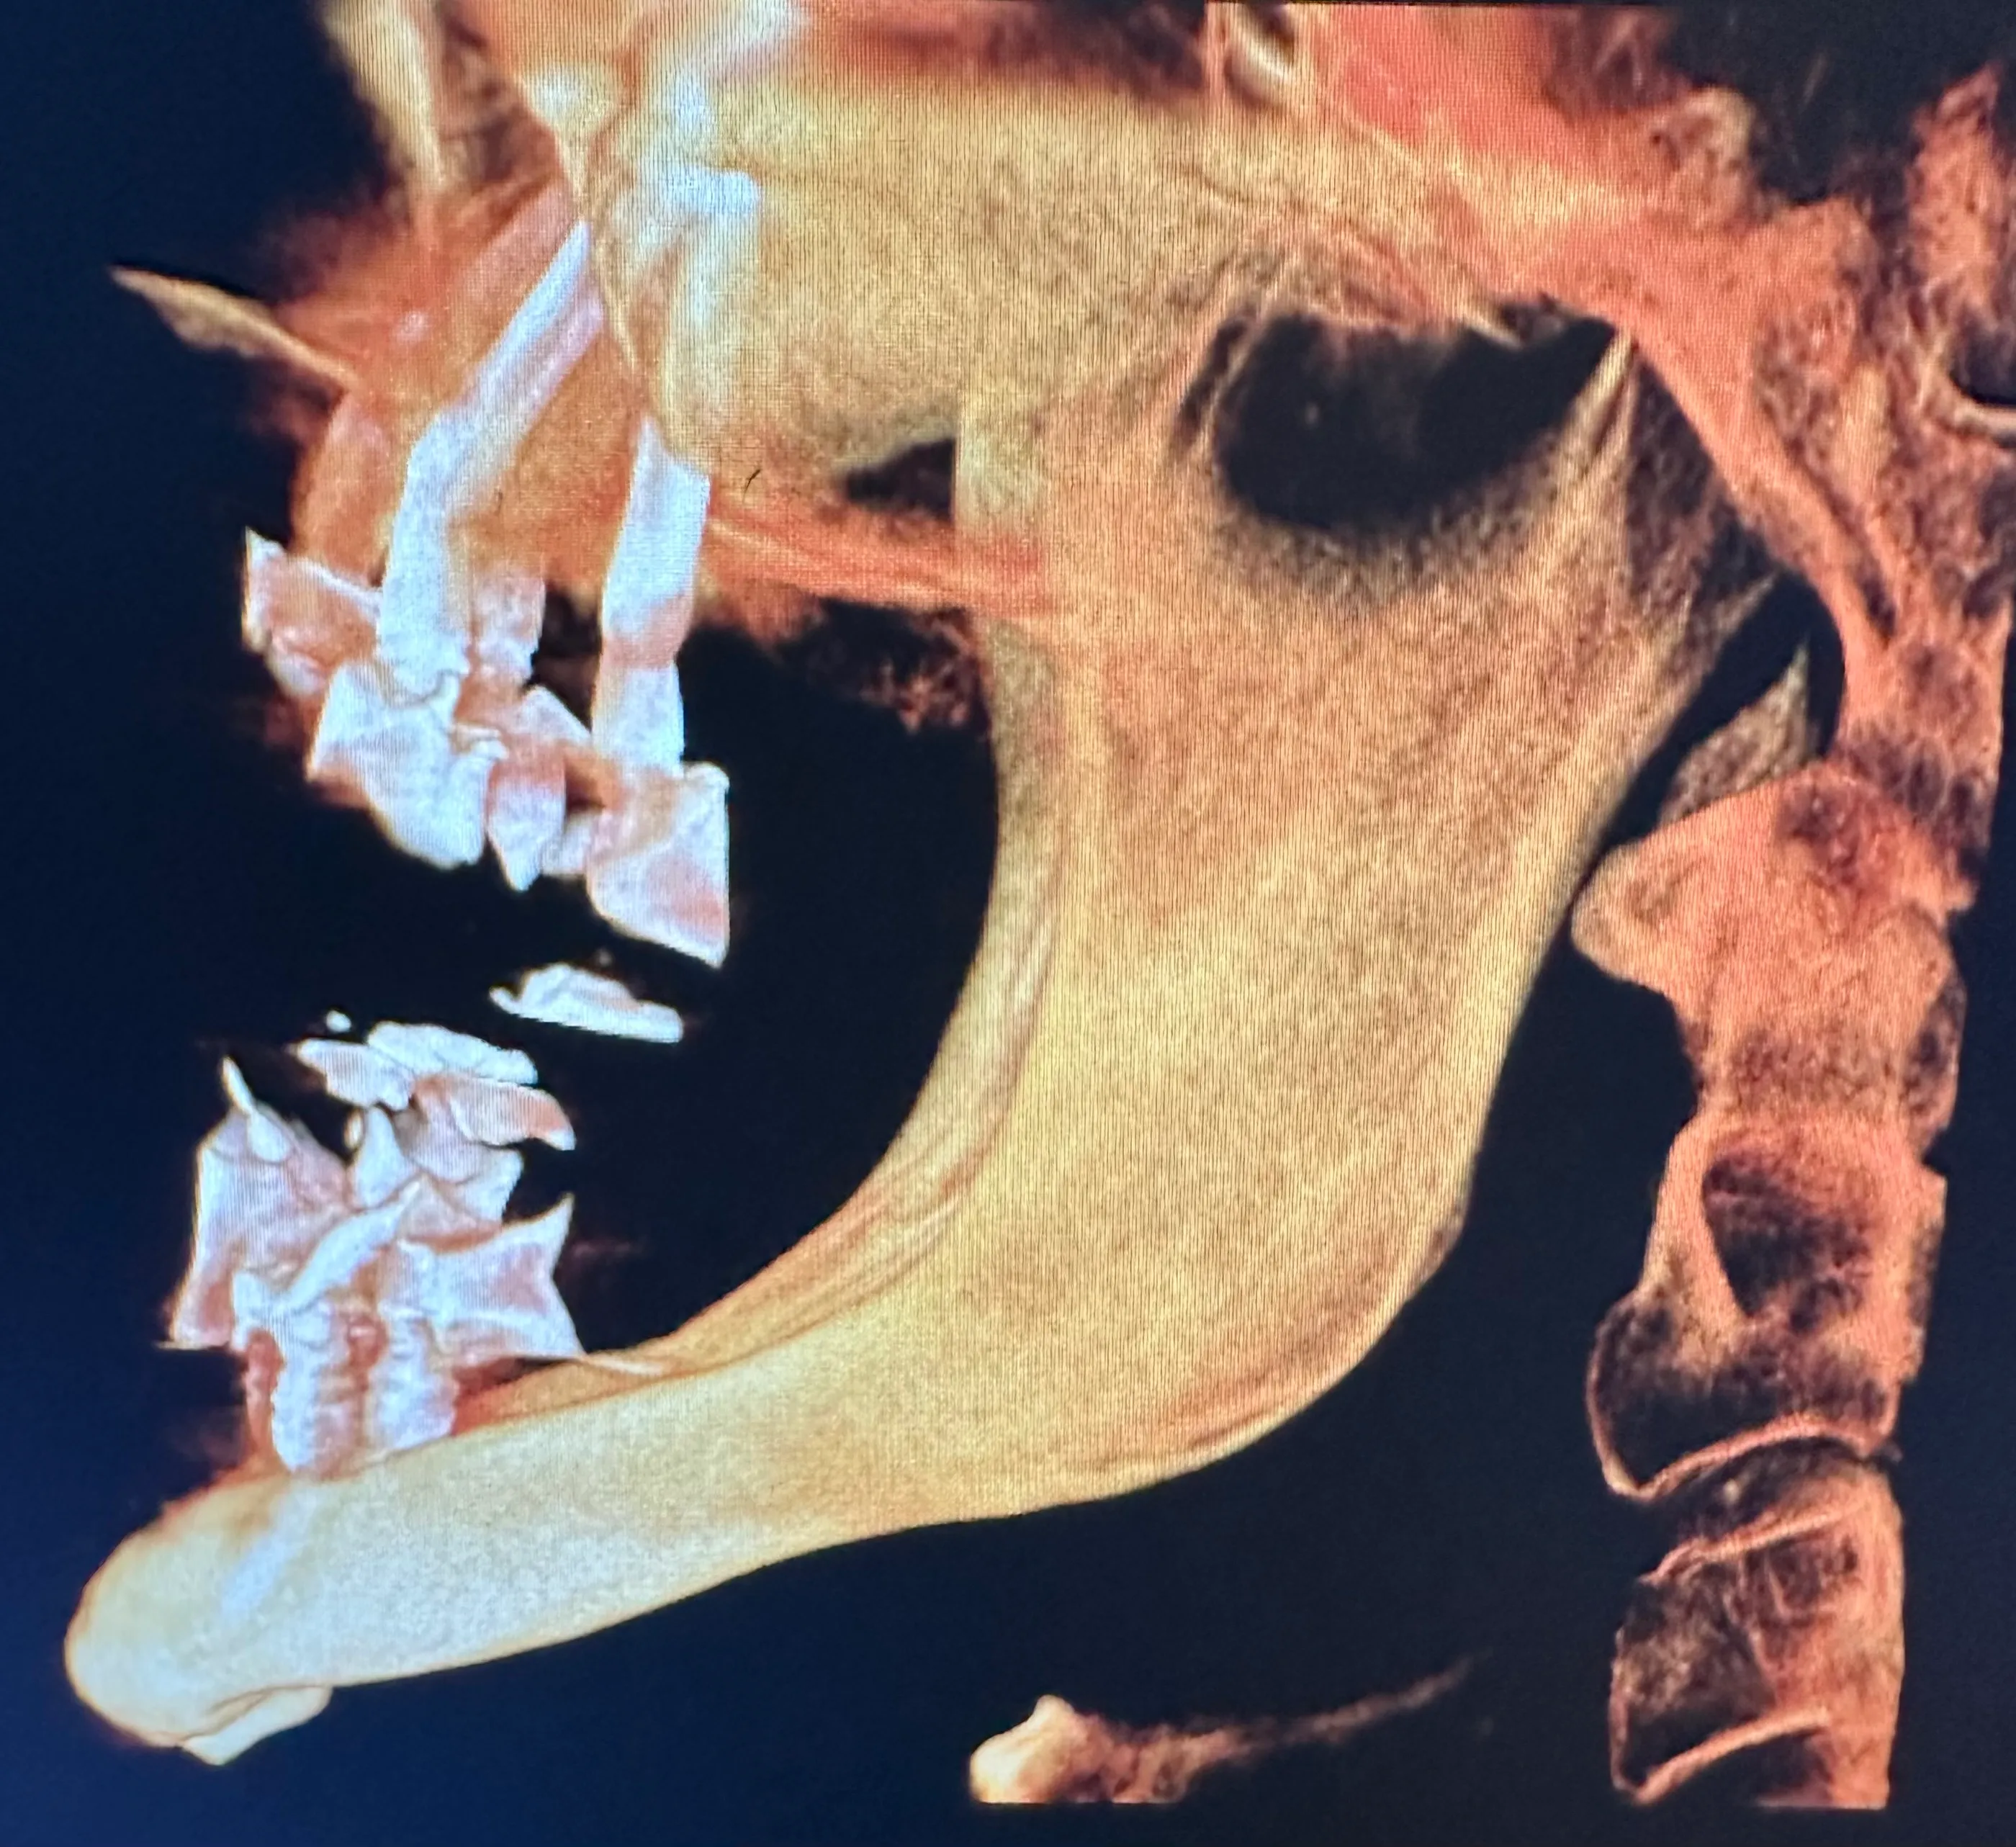

X-ray image of a jaw with dental implants and surgical plates, highlighting the alignment of teeth and orthopedic hardware.

Normally, implants are placed in the maxilla to replace missing teeth in the upper jaw. However, some patients have such severe bone loss that there isn’t enough to place an implant safely. In this case, longer implant screws can be used to reach the cheekbones, which are used as an anchor instead.

Zygomatic dental implants are sometimes called “rescue implants” because they can help patients achieve a fully functional bite and aesthetically pleasing smile when bone grafting isn’t possible.